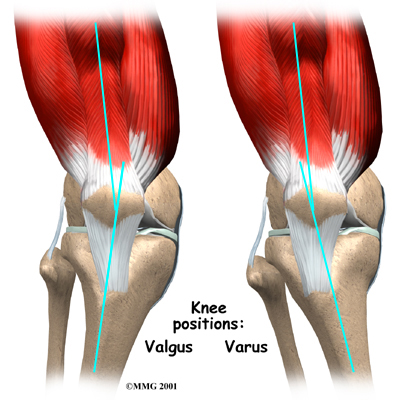

Recently, health experts have found that runners with a weakened or fatigued gluteus medius muscle in the hip are more likely to end up with ITB syndrome. This muscle controls outward movements of the hip. If the gluteus medius isn't doing its job, the thigh tends to turn inward. This makes the knee angle into a knock-kneed position. The ITB becomes tightened against the bursa on the side of the knee. This is also called a valgus deformity of the knee.

People with bowed legs may also be at risk of developing ITB syndrome. The outward angle of the bowed knee makes the lateral femoral condyle more prominent and can make the snapping worse. This condition is also called a varus deformity of the knee.